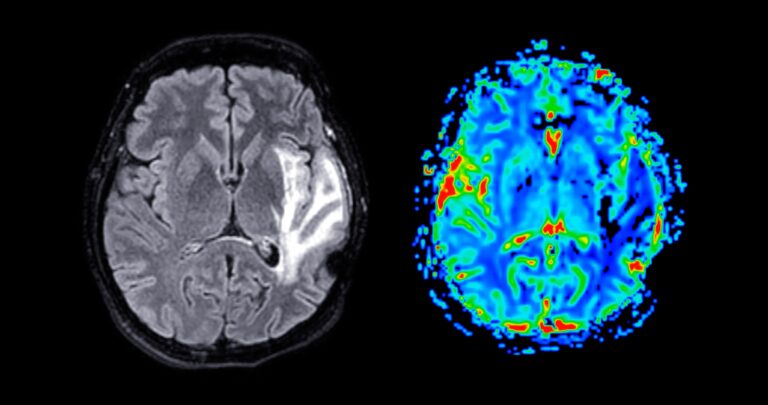

The research, published in Nature, analysed blood samples from nearly 11,500 people and found that more than 1 million over-70s could meet NHS criteria for anti-amyloid treatment, far higher than current estimates. The findings are not a diagnosis but suggest many people carry early disease markers.

Experts say the study could improve early detection, though current treatments are expensive and not widely available on the NHS. The likelihood of Alzheimer’s-related brain changes rises sharply with age, reaching around two-thirds of people over 90.